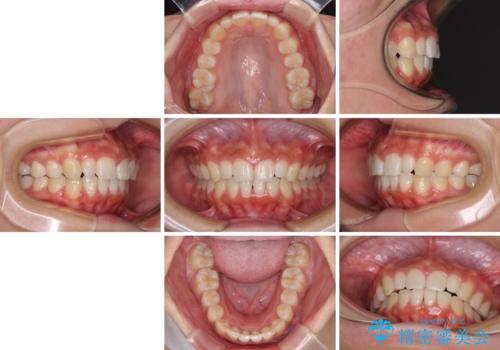

前歯のデコボコを治したい インビザラインによる矯正治療

- 前歯のデコボコ気になるとのことで来院された患者様です。

上下顎ともに歯列全体の後方移動とIPR(歯と歯の間を削る)によってデコボコが解消するように設計し、インビザラインにより治療を行うこととしました。

上顎左右前歯に矮小歯があるため、上顎の奥歯は下顎に対して相対的に前方に位置することになりました。

それでも奥歯の咬みにくさはなく、患者様には大変満足していただきました。